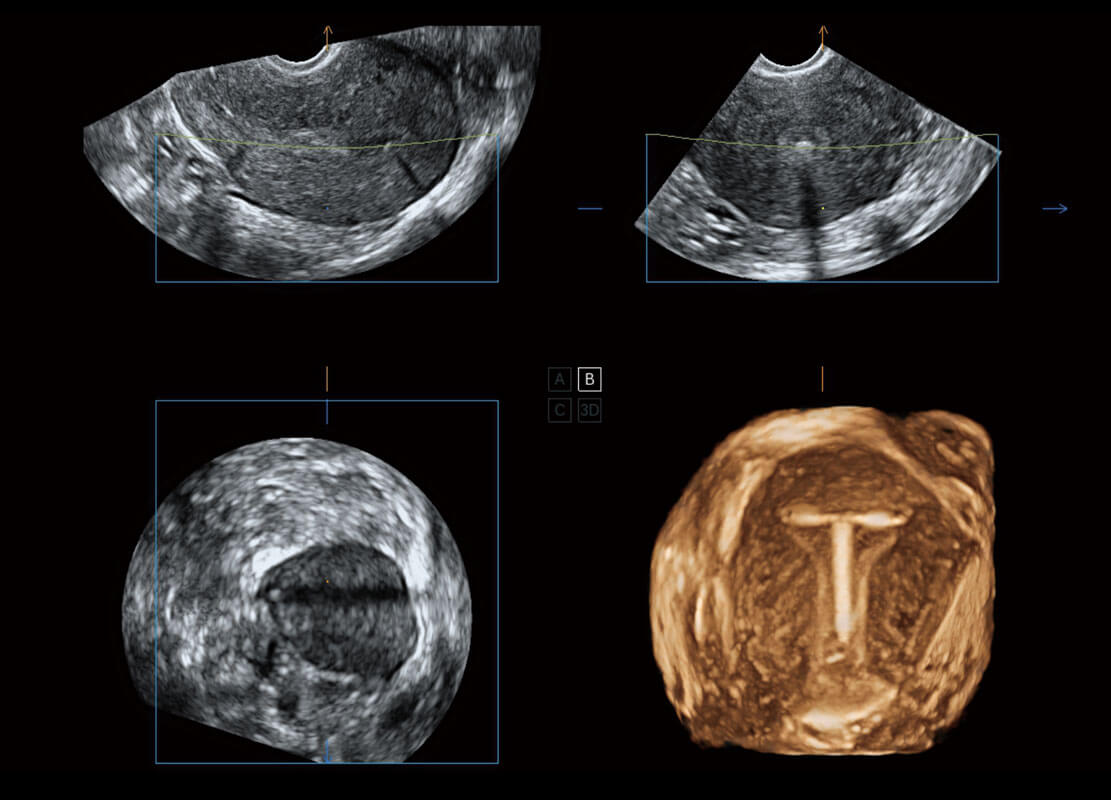

腔内三维-宫内节育器

腔内三维-光影成像

P60为盆底超声检查提供应用方案,多种腔内及腹部容积探头提供从二维、三维到四维的优异图像品质,实时快速三维容积数据获取,专业的测量工具包等人性化设计,为超声医生诊断提供有力保障。